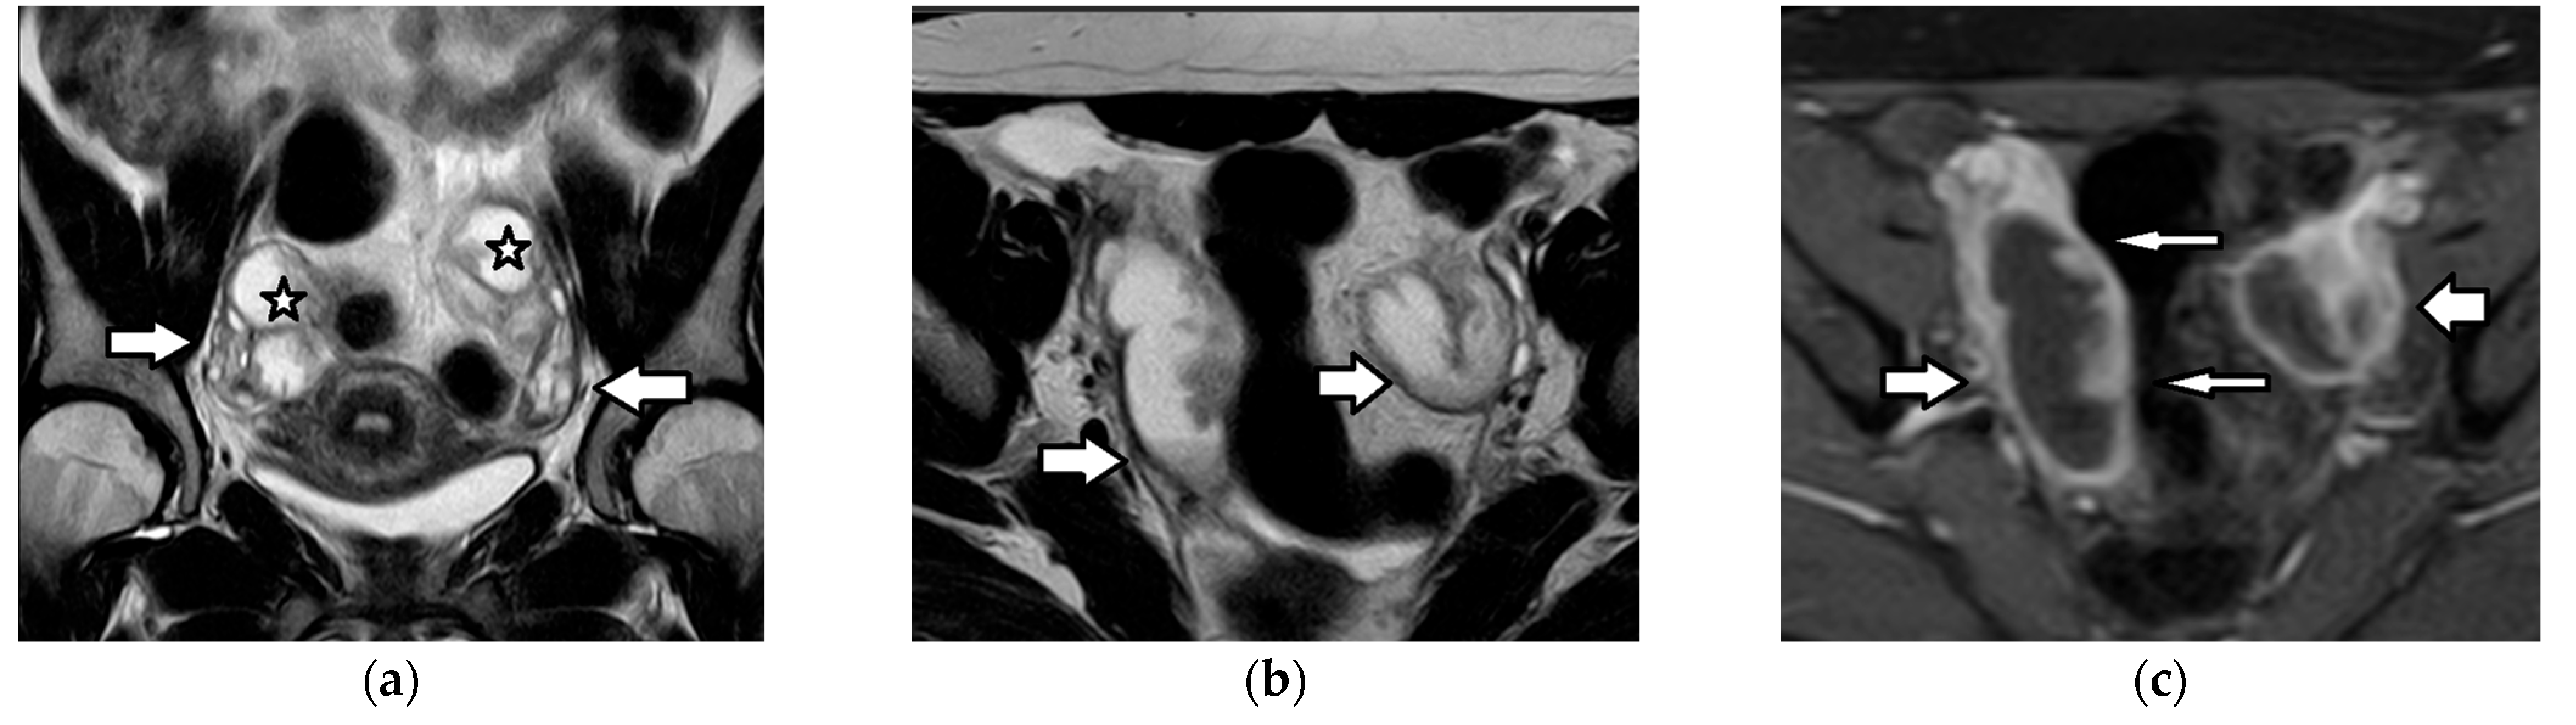

| Dysgerminoma | most common ovarian malignancy 30% of MOGCTs mean age: second, third decades; 10%: first decade bilateral: 10–15% associated with gonadal dysgenesis, gonadoblastoma, chromosomal abnormalities, e.g., Turner syndrome | often diagnosed at an early stage favorable prognosis involvement of pelvic or retroperitoneal lymph nodes recurrence: 13–20% | increased LDH: 95% increased β-hCG (syncytiotrophoblastic giant cells): 5% | large, well-defined, lobulated, mainly solid tumor fibrovascular septa: characteristic

|